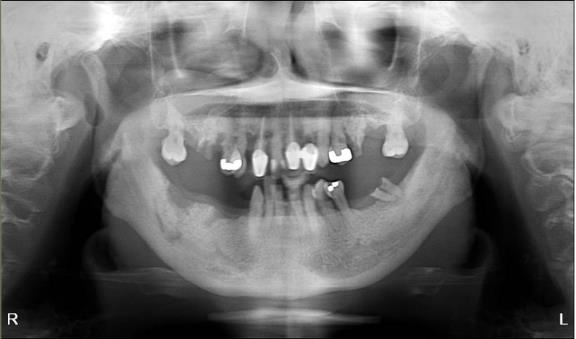

Case 2

The patient is a 54-year-old female with a history of Stage 4 metastatic breast cancer treated with chemotherapy and radiation. She was treated with zoledronic acid (Zometa) beginning in June 2020. The patient was referred to Denver Health OMS by her dentist regarding non-healing extraction sites and additional extractions. In mid-2022, about three months prior to the referral, her dentist had extracted teeth #29 to #31. On examination, the patient had Stage 2 MRONJ along with painful, periodontally compromised, non-restorable teeth. Following a consultation with oncology and infectious disease, the decision was made to debride the MRONJ area and remove the remaining teeth in the operating room with the patient on long-term antibiotic coverage. Within two to three months, MRONJ had recurred and in April 2023, the patient subsequently underwent a right posterior mandibular resection with an antibiotic spacer placed in the resected area.